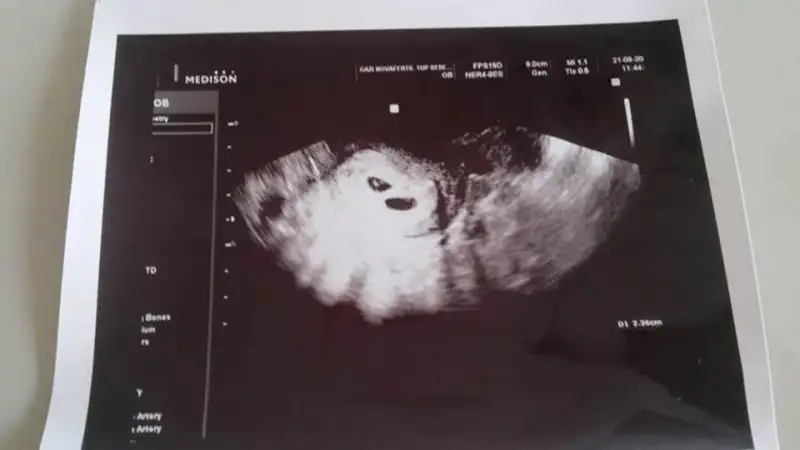

bugün kese görmeye gittik ve iki keseyle karşılaştıkk Rabbim isteyen herkese nas,p etsin inşallah:nazar::KK200: